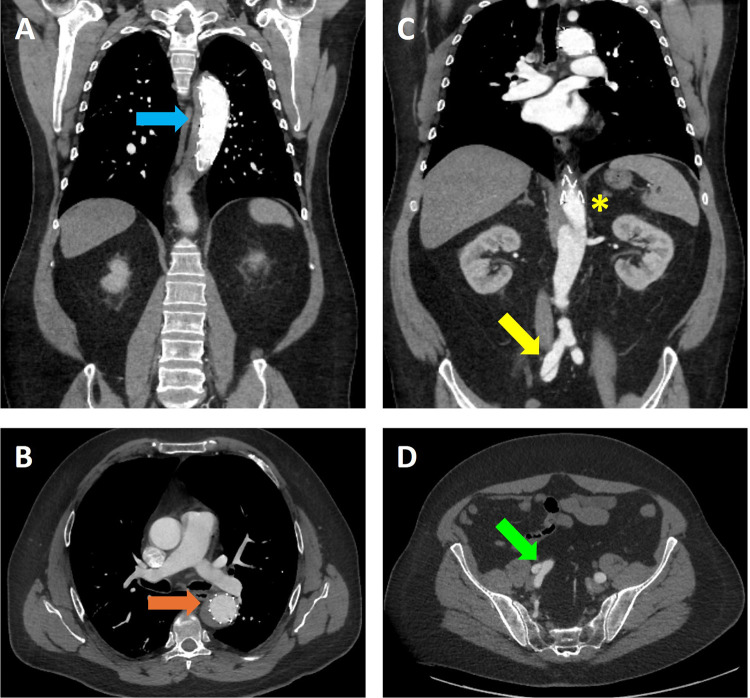

Alpha 1 Antitrypsin Deficiency (AATD) is a genetic condition that results from mutations in the SERPINA1 gene, which can lead to deficient or dysfunctional Alpha 1 Antitrypsin (AAT) protein production. AATD is linked to chronic obstructive pulmonary disease (COPD) and emphysema. In addition to pulmonary manifestations, AATD has also been associated with vascular pathology due to excessive protease activity, tissue degradation, and vessel stiffening. Early AATD diagnosis is crucial to prevent progressive lung damage and associated pathologies. Here, we present case reports of two patients with AATD from the Temple University Hospital Outpatient Clinic, who exhibited aneurysms of the aorta and splenic artery. AATD should be considered a genetic risk factor for aneurysms and vascular diseases, necessitating cardiovascular monitoring in affected individuals. This report emphasizes both the need for heightened awareness of AATD as a potential etiology of unexplained vascular aneurysms, as well as the need for screening for vascular pathology in patients with AATD-associated COPD and emphysema to facilitate early intervention and improve patient outcomes.

Abstract Image